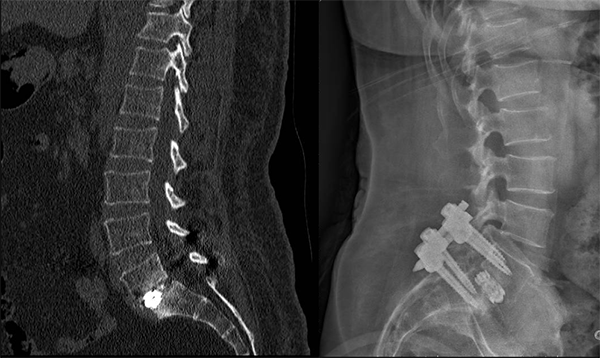

術(shù)前影像

根據(jù)覃阿姨門診腰椎磁共振顯示:腰5椎體I度滑脫伴雙側(cè)椎弓峽部裂,腰5骶1椎間盤突出合并椎管狹窄,我院脊柱外科主任胡朝暉博士及其團(tuán)隊(duì)討論研究后認(rèn)為,患者身型重度肥胖,140cm的身高體重高達(dá)72公斤,BMI指數(shù)達(dá)36.7,屬于超重范圍,開刀手術(shù)難度將升級,存在易出血多、感染幾率升高、術(shù)口相對難愈合等風(fēng)險(xiǎn),但內(nèi)鏡下腰椎融合手術(shù)較傳統(tǒng)開放手術(shù)相比,僅需要5個(gè)1.5cm的皮膚切口,具有創(chuàng)傷更小、出血更少、切口感染概率低、術(shù)后恢復(fù)快、病人術(shù)后疼痛輕等優(yōu)點(diǎn),因此內(nèi)鏡下腰椎融合手術(shù)更適合覃阿姨。

手術(shù)很順利,脊柱外科在微創(chuàng)置釘技術(shù)下將滑脫完全復(fù)位,術(shù)后覃阿姨腰痛逐漸緩解,她對治療效果非常滿意,現(xiàn)已康復(fù)出院。

術(shù)后影像